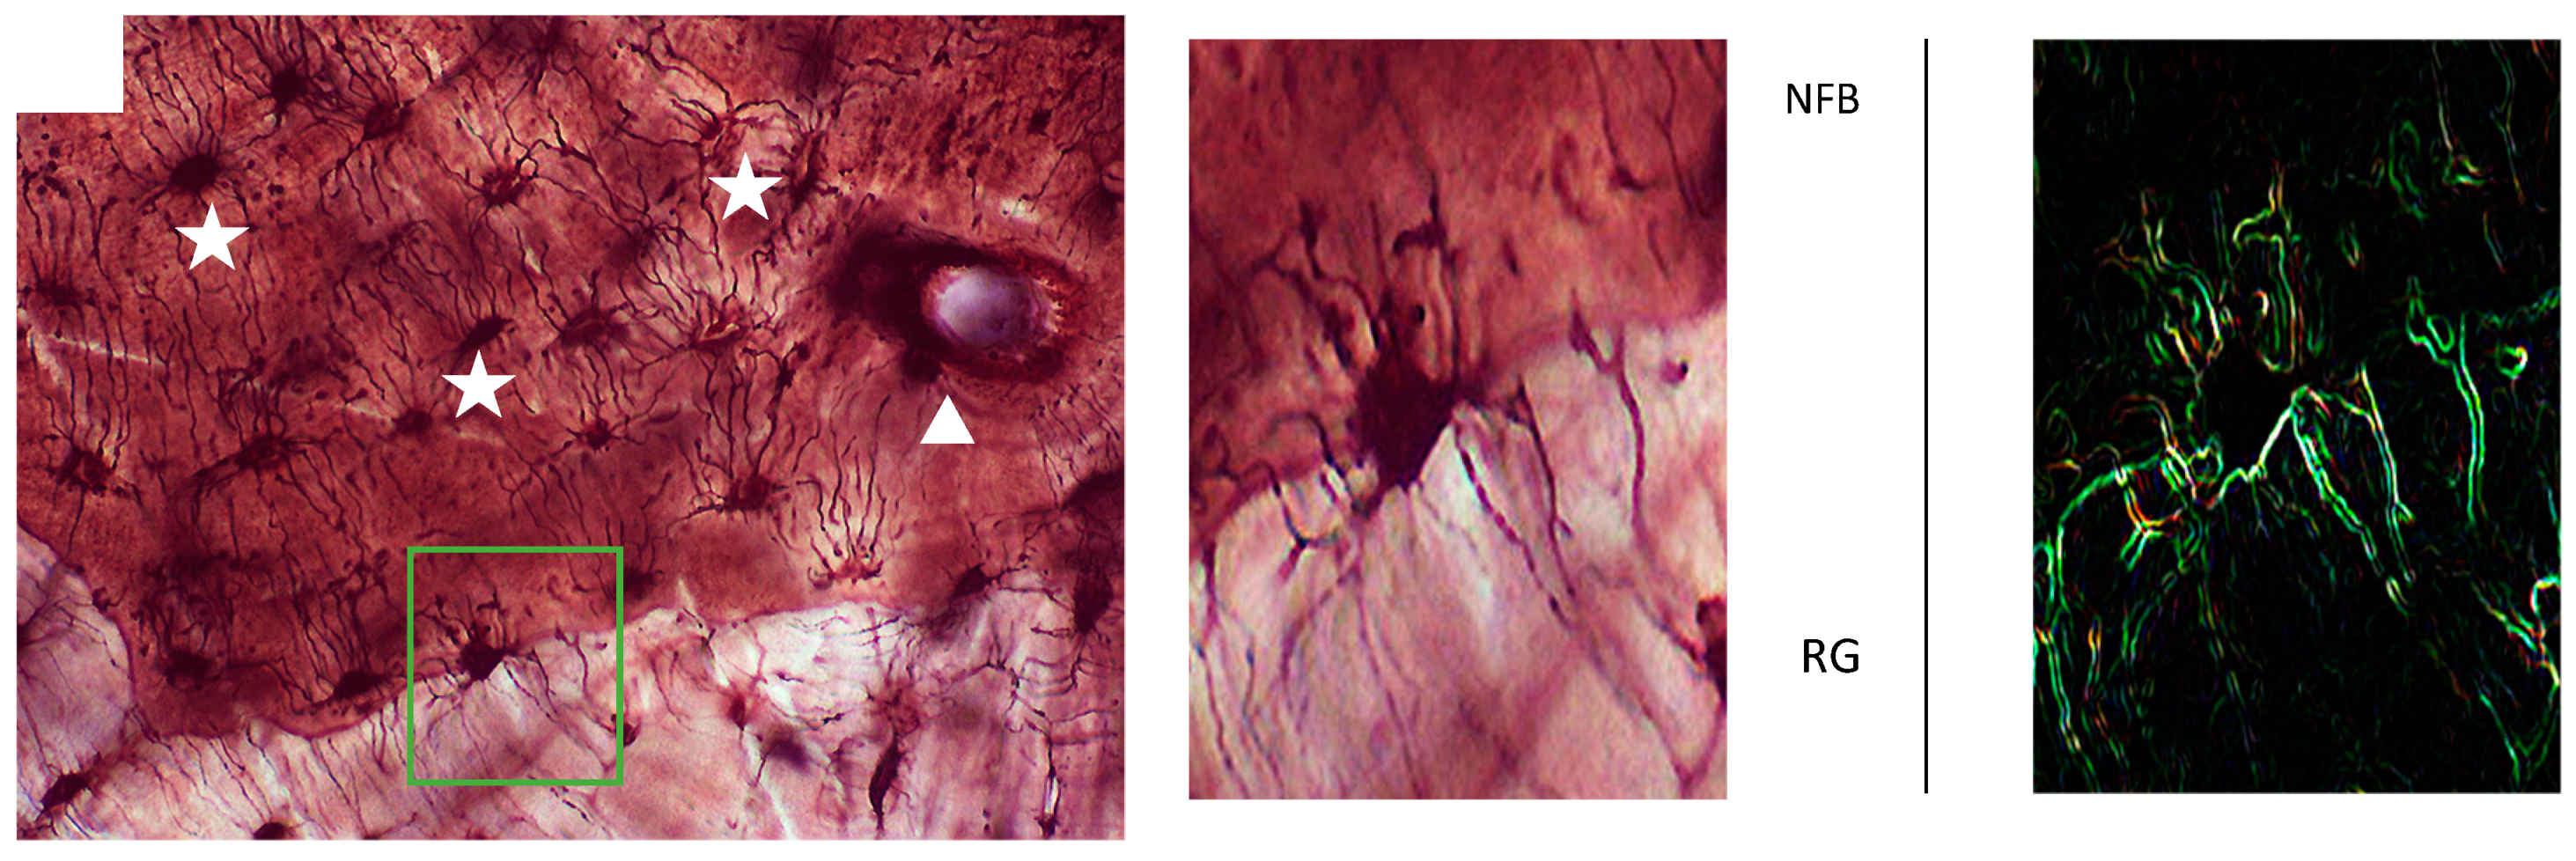

2. Materials and Methods